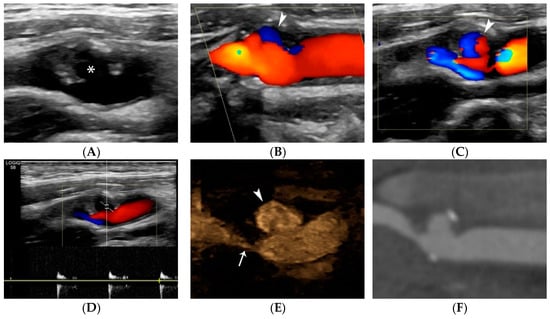

- Rafailidis, V.; Chryssogonidis, I.; Tegos, T.; Kouskouras, K.; Charitanti-Kouridou, A. Imaging of the ulcerated carotid atherosclerotic plaque: A review of the literature. Insights Imaging 2017, 8, 213–225. [Google Scholar] [CrossRef]

- Hamada, O.; Sakata, N.; Ogata, T.; Shimada, H.; Inoue, T. Contrast-enhanced ultrasonography for detecting histological carotid plaque rupture: Quantitative analysis of ulcer. Int. J. Stroke 2016, 11, 791–798. [Google Scholar] [CrossRef] [PubMed]

- ten Kate, G.L.; van Dijk, A.C.; van den Oord, S.C.; Hussain, B.; Verhagen, H.J.; Sijbrands, E.J.; van der Steen, A.F.; van der Lugt, A.; Schinkel, A.F. Usefulness of contrast-enhanced ultrasound for detection of carotid plaque ulceration in patients with symptomatic carotid atherosclerosis. Am. J. Cardiol. 2013, 112, 292–298. [Google Scholar] [CrossRef] [PubMed]

- Rafailidis, V.; Charitanti, A.; Tegos, T.; Rafailidis, D.; Chryssogonidis, I. Swirling of microbubbles: Demonstration of a new finding of carotid plaque ulceration on contrast-enhanced ultrasound explaining the arterio-arterial embolism mechanism. Clin. Hemorheol. Microcirc. 2016, 64, 245–250. [Google Scholar] [CrossRef]

- Rafailidis, V.; Chryssogonidis, I.; Xerras, C.; Nikolaou, I.; Tegos, T.; Kouskouras, K.; Rafailidis, D.; Charitanti-Kouridou, A. A comparative study of color Doppler imaging and contrast-enhanced ultrasound for the detection of ulceration in patients with carotid atherosclerotic disease. Eur. Radiol. 2019, 29, 2137–2145. [Google Scholar] [CrossRef]

- Lyu, Q.; Tian, X.; Ding, Y.; Yan, Y.; Huang, Y.; Zhou, P.; Hui, P. Evaluation of Carotid Plaque Rupture and Neovascularization by Contrast-Enhanced Ultrasound Imaging: An Exploratory Study Based on Histopathology. Transl. Stroke Res. 2021, 12, 49–56. [Google Scholar] [CrossRef]